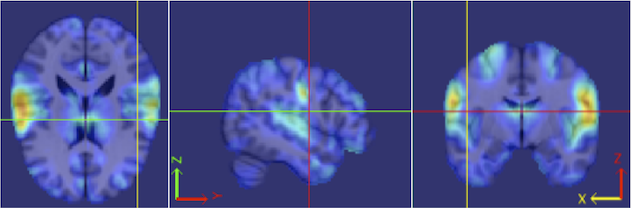

Our procedure is as follows. Each fMRI scan was separated into left and right hemispheres. Thus, each hemisphere contained voxels. Similar to standard group ICA (Calhoun et al., 2001b), a dimension reduction using PCA was applied to each hemisphere of each subject. 15 PCs are obtained for each hemisphere. A group data matrix was generated by concatenating the reduced data of both hemispheres of the 20 subjects in the temporal domain. Thus, the aggregated matrix has dimension , where , , and . Our algorithm of homotopic group ICA is then applied on this matrix. Fifteen estimated independent components are postulated by H-gICA. As shown in Figure 12, out of the 15 components, several brain networks were found including: the visual network 12, the default mode network 12, the auditory network 12, and the motor network 12. Compared with the ICs obtained from ordinary gICA, shown in 12, 12, 12 and 12, H-gICA improves the estimation of all of these sources by yielding substantially more clearly delineated networks.